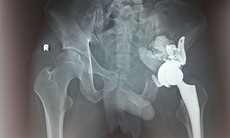

Điều trị ngoại khoa: Điều trị ngoại khoa thường được áp dụng khi các phương pháp điều trị nội khoa và vật lý trị liệu không hiệu quả, hoặc khi bệnh lý đã tiến triển đến mức nghiêm trọng, gây ra tàn phế.